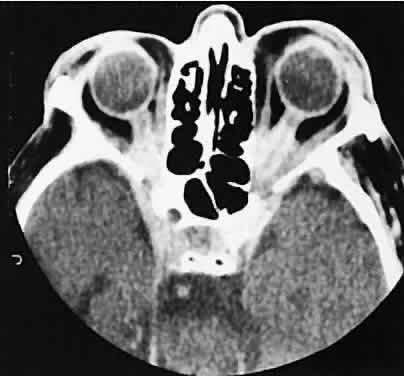

Lymphomatous involvement of the lacrimal gland resembles inflammatory dacryoadenitis radiographically. The enlarged lacrimal gland conforms to the shape of the globe, and the adjacent bone is normal (Fig. 18). We are aware of three high-grade lymphomas that affected the orbit and lacrimal gland and indented the globe, but this is distinctly unusual. Non-Hodgkin's B-cell lymphomas represent the most common type of lymphoma to affect the orbit. Literally any structure in the orbit can be subject to lymphomatous involvement; therefore, a lymphoma should be suspected in the presence of any amorphous isointense infiltrative process.

Fig. 18. Axial (A) and coronal (B) views of lacrimal gland lymphoma. There is homogenous enhancement of the enlarged lacrimal gland. Compared with Fig. 6, there is no difference.